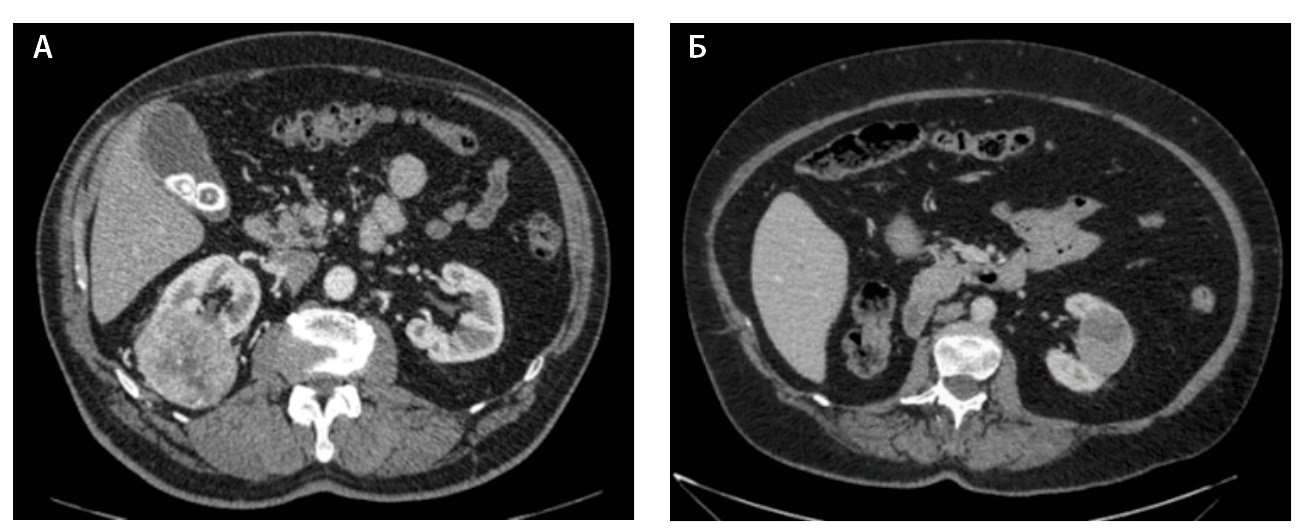

Компьютерная томография (КТ) с внутривенным контрастным усилением широко используется как метод диагностики и первичного стадирования скПКР. В настоящее время наиболее значимыми характеристиками опухоли для предоперационного стадирования и планирования хирургического лечения скПКР признаны расположение, размер опухоли и признаки ее инвазивного роста [3–6], а структура и характер контрастирования позволяют дифференцировать типы ПКР, но ни один из этих показателей не дает возможности достоверно прогнозировать степень дифференцировки опухоли. Структура скПКР любой степени дифференцировки, как правило, гетерогенная с наличием солидного и кистозного компонентов. Признаки инвазивного роста опухоли, наличие метастазов позволяют предположить низкую степень дифференцировки опухоли, однако не являются достоверными признаками. Как видно на рис. 1, скПКР разной степени дифференцировки по данным КТ выглядят практически идентично: в обоих случаях визуализируется опухолевый тромб в почечной вене с распространением в просвет нижней полой вены. Такие характеристики, как размер опухоли, пофазное накопление контрастного вещества и градиент накопления контрастного вещества при КТ-исследовании, также не являются строго специфичными для разных степеней дифференцировки скПКР (рис. 2).

Рис. 1. Светлоклеточный почечно-клеточный рак: А – Grade 4 (данные компьютерной томографии пациентки Б.), Б – Grade 2 (данные компьютерной томографии пациента Г.). На обоих снимках кортико-медуллярная фаза исследования: гиперваскулярная опухоль солидно-кистозного строения, замещающая паренхиму левой почки, опухолевый тромб в просвете левой почечной вены с распространением в нижнюю полую вену; метастически измененный регионарный лимфатический узел

Рис. 2. Светлоклеточный почечно-клеточный рак. А – Grade 1 (данные компьютерной томографии пациента С.), кортико-медуллярная фаза исследования: трансмуральная опухоль правой почки размером 6,6 см, с четкими и ровными контурами, прилежит к синусу почки, опухоль имеет солидно-кистозное строение, солидный компонент опухоли накапливает контрастное вещество (КВ) менее интенсивно, чем кортикальный слой почки, градиент накопления КВ солидным компонентом опухоли 50–60 HU. Б – Grade 4 (данные компьютерной томографии пациентки Щ.), кортико-медуллярная фаза исследования: трансмуральная опухоль левой почки размером 5,2 см, с четкими и ровными контурами, прилежит к синусу почки, опухоль имеет солидно-кистозное строение, солидный компонент опухоли накапливает КВ менее интенсивно, чем кортикальный слой почки, градиент накопления КВ солидным компонентом опухоли 45–60 HU